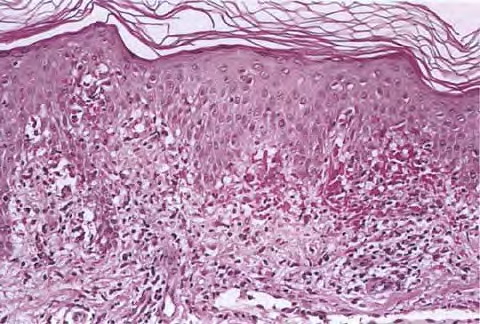

Pernio = الشرث Pernio (Chilblain) Pernio (chilblain) is a distinct form of cold-induced injury in which humidity, in addition to cold, plays a role in inducing the condition . There are acute and chronic presentations. Chilblains classically presents in young to middle-aged women as painful, burning, and/or pruritic erythematous to violaceous or cyanotic macules, papules, […]